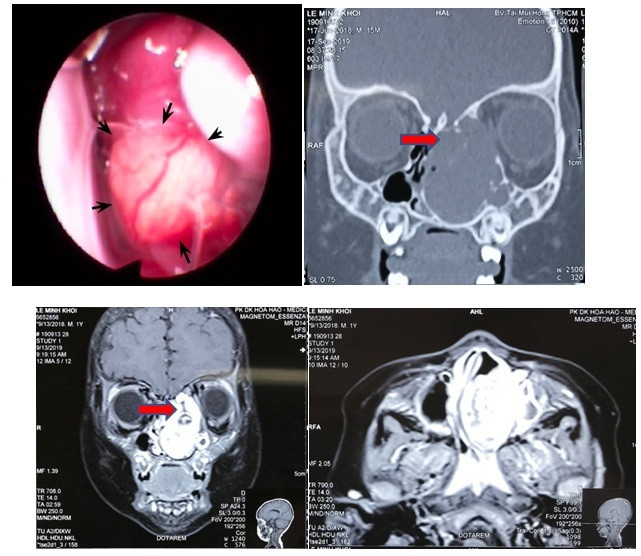

![]() |

| Hình ảnh nội soi và CT scan khối u lớn vùng hốc mũi trái. Ảnh: BVCC |

Tại BV Tai Mũi Họng TP.HCM, bác sĩ tiến hành các xét nghiệm và đã chẩn đoán vùng hốc mũi trái của bé có khối u kích thước khoảng 35mm. Khối u này gây biến dạng, hủy xương sàng, xương thành trong hốc mắt và một phần mềm sọ, đồng thời, khối u đè ép các cấu trúc hốc mũi, chèn ép đỉnh hốc mắt và hậu nhãn bên trái.

Đây là trường hợp khó do khối u nằm ở sát nền sọ nên nguy cơ chảy dịch não tủy trong lúc phẫu thuật là rất cao.